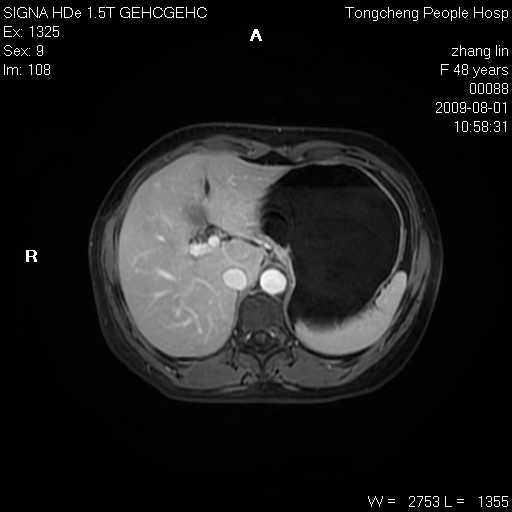

女,48岁。健康体检,彩超发现右肾占位性病变。平素健康。

临床诊断:右肾占位性病变,性质待定(囊肿?肿瘤?)。

上中腹部mr平扫+增强扫描,图像如下:

右肾上极见一类圆形病灶,t1wi呈等信号t2wi呈等高混杂信号,三期增强无强化,边界清---考虑囊肿出血。

同反相位均表现为等信号,病变无强化,考虑含蛋白的囊肿可能,弥散加权相或许有些帮助,